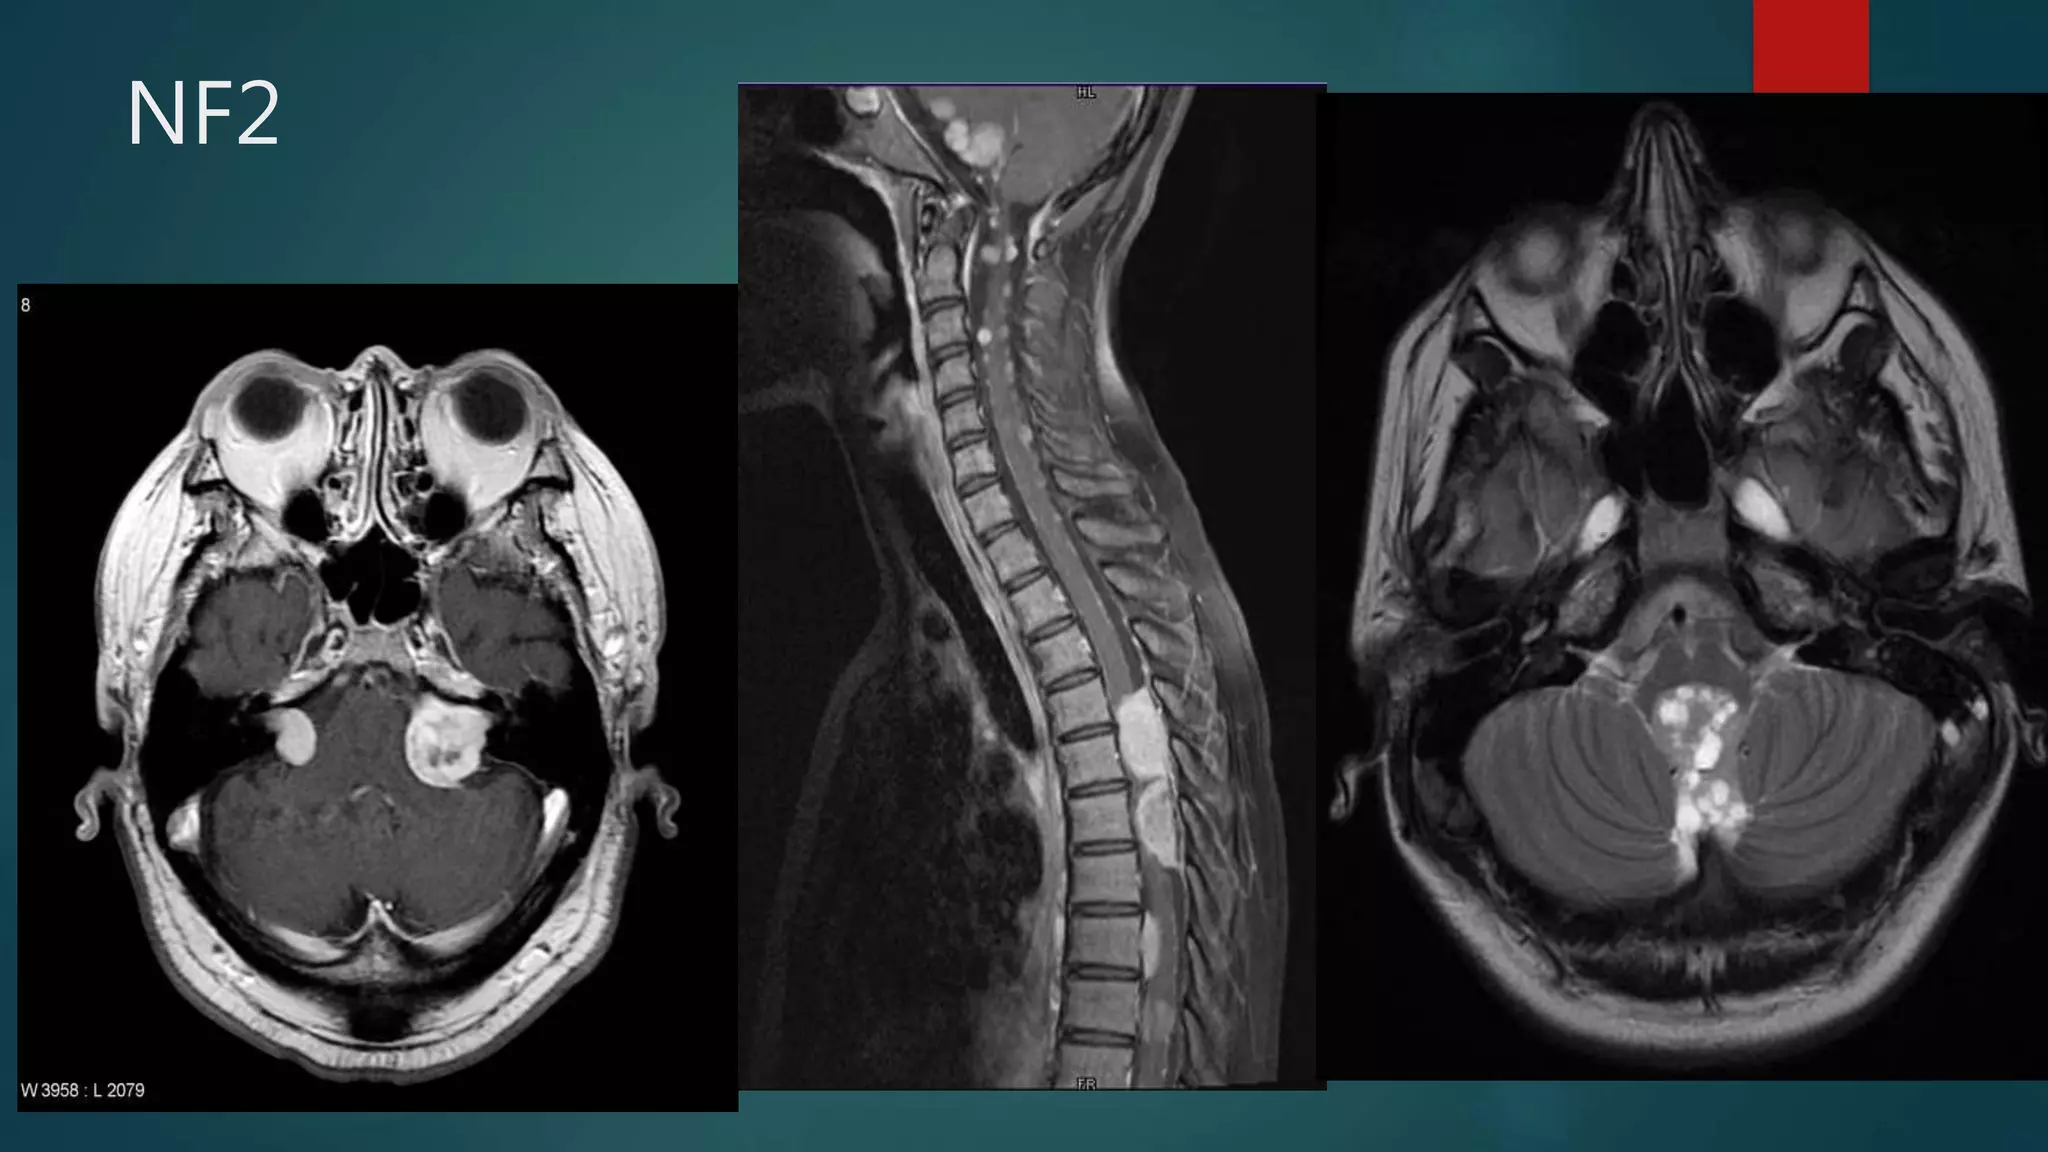

NF2

Mnemonics

 MISME

• M: multiple

• I: inherited

• S: schwannomas

• M: meningiomas and

• E: ependymomas

 Rule of 2s

• neurofibromatosis type 2

• chromosome 22 (22q12) gene location

• bilateral vestibular schwannomas

• presents in 2nd-4th decades (around 20 years)

• initial prevalence estimated to be 1:200,000

• #31 Post contrast T1 axial imaging demonstrates bilateral enhancing masses in the cerebellopontine angle, larger on the left. Both can be seen extending into the internal acoustic meatii and are consistent with acoustic schwannomas. The fact that they are bilateral almost certainly indicates that the patient has NF2.  There are multiple enhancing nodular lesions spread throughout all the spinal canal and going through some vertebral foramina Mixed solid-cystic mass arising from the fourth ventricle and causing mass effect on the brainstem. There was also resultant obstructive hydrocephalus, not shown here. The mass appears to ‘ooze’ out of the foramen of Magendie. There was no associated spinal lesion. Classical ‘plastic’ ependymoma